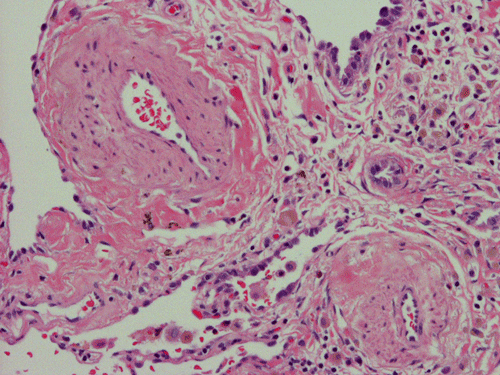

At scanning magnification (Panel A), the lung parenchyma is replaced by some coalescing fibrous nodules. The degree of involvement is variable at different fragments (Panel B and C). In the less affected areas, there are some fibrotic thickening of the septa (Panel C). In some areas, the changes are minimal and the pleural appear to be uninvolved (Panel D and E). In low to medium magnifications, these nodules of fibrosis contains a large number of hemosiderin laden macrophages (Panel F and G) admixed with fibrous tissue. The diagnostic tissue, however, is present in areas with increased cellularity. In these areas, there is a background of cells with a moderate amount of cytoplasm and bland nuclei. Some of these nuclei have kidney shape (arrow in Panel H). In some areas, many of the nuclei have a deep nuclear groove that resemble a coffee bean (arrow in Panel I). In the third type of areas, the nuclear grooving is not distinct (Panel J). Prominent eosinophilic infiltrations are almost always present. Immunohistochemistry on CD1a revealed many positive cells (Panel L). Also present in the specimen are multiple small blood vessels with thickened intima (Panel K). A Movat pentachrome stain demonstrates an internal elastic layer in these vessels and confirms that these are arteries (Panel M and N).

In the end stage, the exhausted lesions are predominantly fibrotic and largely depleted of LCs. In some regions, the fibrosis may surround cystic spaces of variable diameter to form large areas of honeycombing. This is especially predominant in the upper lobes. In cases where parenchymal scaring is present, the pulmonary function will be largely compromised. At this stage, both pulmonary function tests and radiologic findings may suggest diffuse lung disease, but biopsy will show stellate fibrotic lesions centered on the terminal airways with no identifiable interstitial inflammation. Pulmonary vasculopathy (in areas of lung remote from parenchymal nodules) is also seen in late stage PLCH. Vasculopathy manifests as intimal fibrosis, medial hypertrophy or luminal obliteration involving both venules and arteries. This may account for pulmonary hypertension seen late in PLCH.